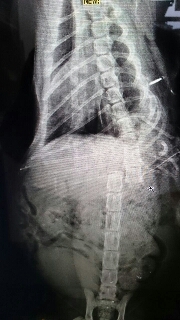

主題: 浪狗圍攻脊椎斷裂下肢癱瘓的橘色公貓 申請者姓名: 黃意如 花色: 申請日期: 2014-12-24 16:36:05 申請者部落格: 申請者臉書網址: 所在縣市/合作醫院: 新北市/哲生動物醫院 治療費用: 13840元 需求人數: 16人 已結案 (2015-02-24 11:56:48) 報名人員: Norman Wu(已付款)、Han Han Wang(已付款)、皮皮&米漿(已付款)、fifihsu(已付款)、陳曉莫(已付款)、ONE(已付款)、Sica(已付款)、apple(已付款)、Jessica Chen(已付款)、ethan(已付款)、berry(已付款)、Snow Chen(已付款)、Tosca Weng(已付款)、Ricky(已付款)、Yen-Yuan Wang(已付款)、Swe Chang(已付款)、 候補人員: nadia、Ppn Huang、 動物病情說明: 凌晨負責掃街的清潔阿姨通報,4隻浪狗圍攻咬傷了一隻貓咪,放下工作趕緊過去救援,發現貓咪受傷路倒,當靠近時,貓咪緊張用前肢拖行,後腳完全無法用力。

打電話把睡夢中的醫生Call來,檢查後,發現貓咪的身上有三處傷口,背部傷口特別嚴重。經過X光檢查,發現脊椎骨折,100%錯位。4根肋骨斷裂,開刀裝置引流管,同時傷口做清創手術。

醫生確判貓咪應該終生癱瘓。